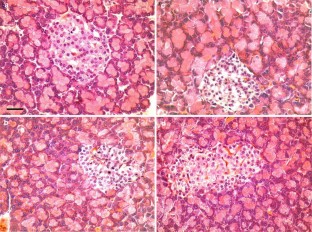

Diabetes mellitus is a common but serious metabolic disorder associated with many functional and structural complications. Glucose metabolism is disturbed due to an absolute or relative insulin deficiency. The experiment was carried out to determine the effect of melatonin on blood glucose and insulin concentrations, and histopathology of pancreatic β-cells in streptozotocin (STZ)-induced diabetic rats. The rats were randomly allocated into one of the four experimental groups: group A (control), group B (diabetic untreated), group C (diabetic treated with melatonin for 6 weeks) and group D (diabetic treated with melatonin for 8 weeks); each group contained ten animals. Diabetes was induced in B, C and D groups by a single intraperitoneal (i.p.) injection of STZ (50 mg/kg, freshly dissolved in 5 mmol/l citrate buffer, pH 4.5). The rats in melatonin-treated groups were subjected to the daily i.p injection of 10 mg kg−1 of melatonin for 6 or 8 weeks starting the day after STZ injection. Control and diabetic untreated rats were injected with the same volume of isotonic NaCl as the melatonin treated groups. Almost all insulin-positive β-cells were degranulated, degenerated or necrotic in the STZ-treated rats leading to decrease in insulin secretion and an increase in blood glucose concentration. Melatonin treatment caused a sharp decrease in the elevated serum glucose, a slight increase in the lowered serum insulin concentrations and small partial regeneration/proliferation of β-cells of islets. It is concluded that the hypoglycemic action of melatonin could be partly due to small amelioration in the β-cells of pancreatic islets causing a slight increase in insulin secretion, it is mostly due to the extrapancreatic actions of the melatonin.

Fig. 1

Fig. 2